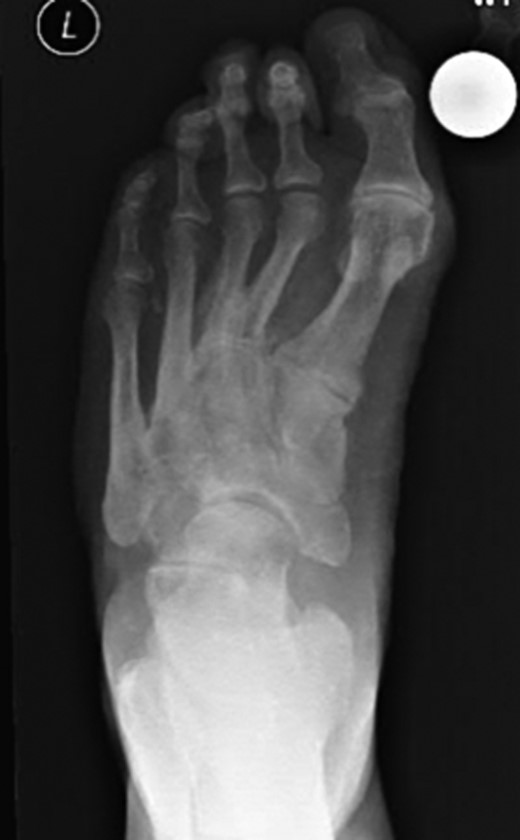

Dorsoplanter, lateral and oblique radiographs demonstrated an additional bone immediately distal to the middle cuneiform articulating with the second metatarsal base and middle cuneiform. Second and third metatarsals were shorßt in comparison with normal (Figs 1–3). Osteoarthritis was seen in all TMTJs and the first MTPJ. A computed tomography (CT) scan confirmed the presence of the additional bone and degenerative joint disease (Figs 4 and 5).

Dorsoplanter radiograph of the left foot with the clearly visible additional middle cuneiform.